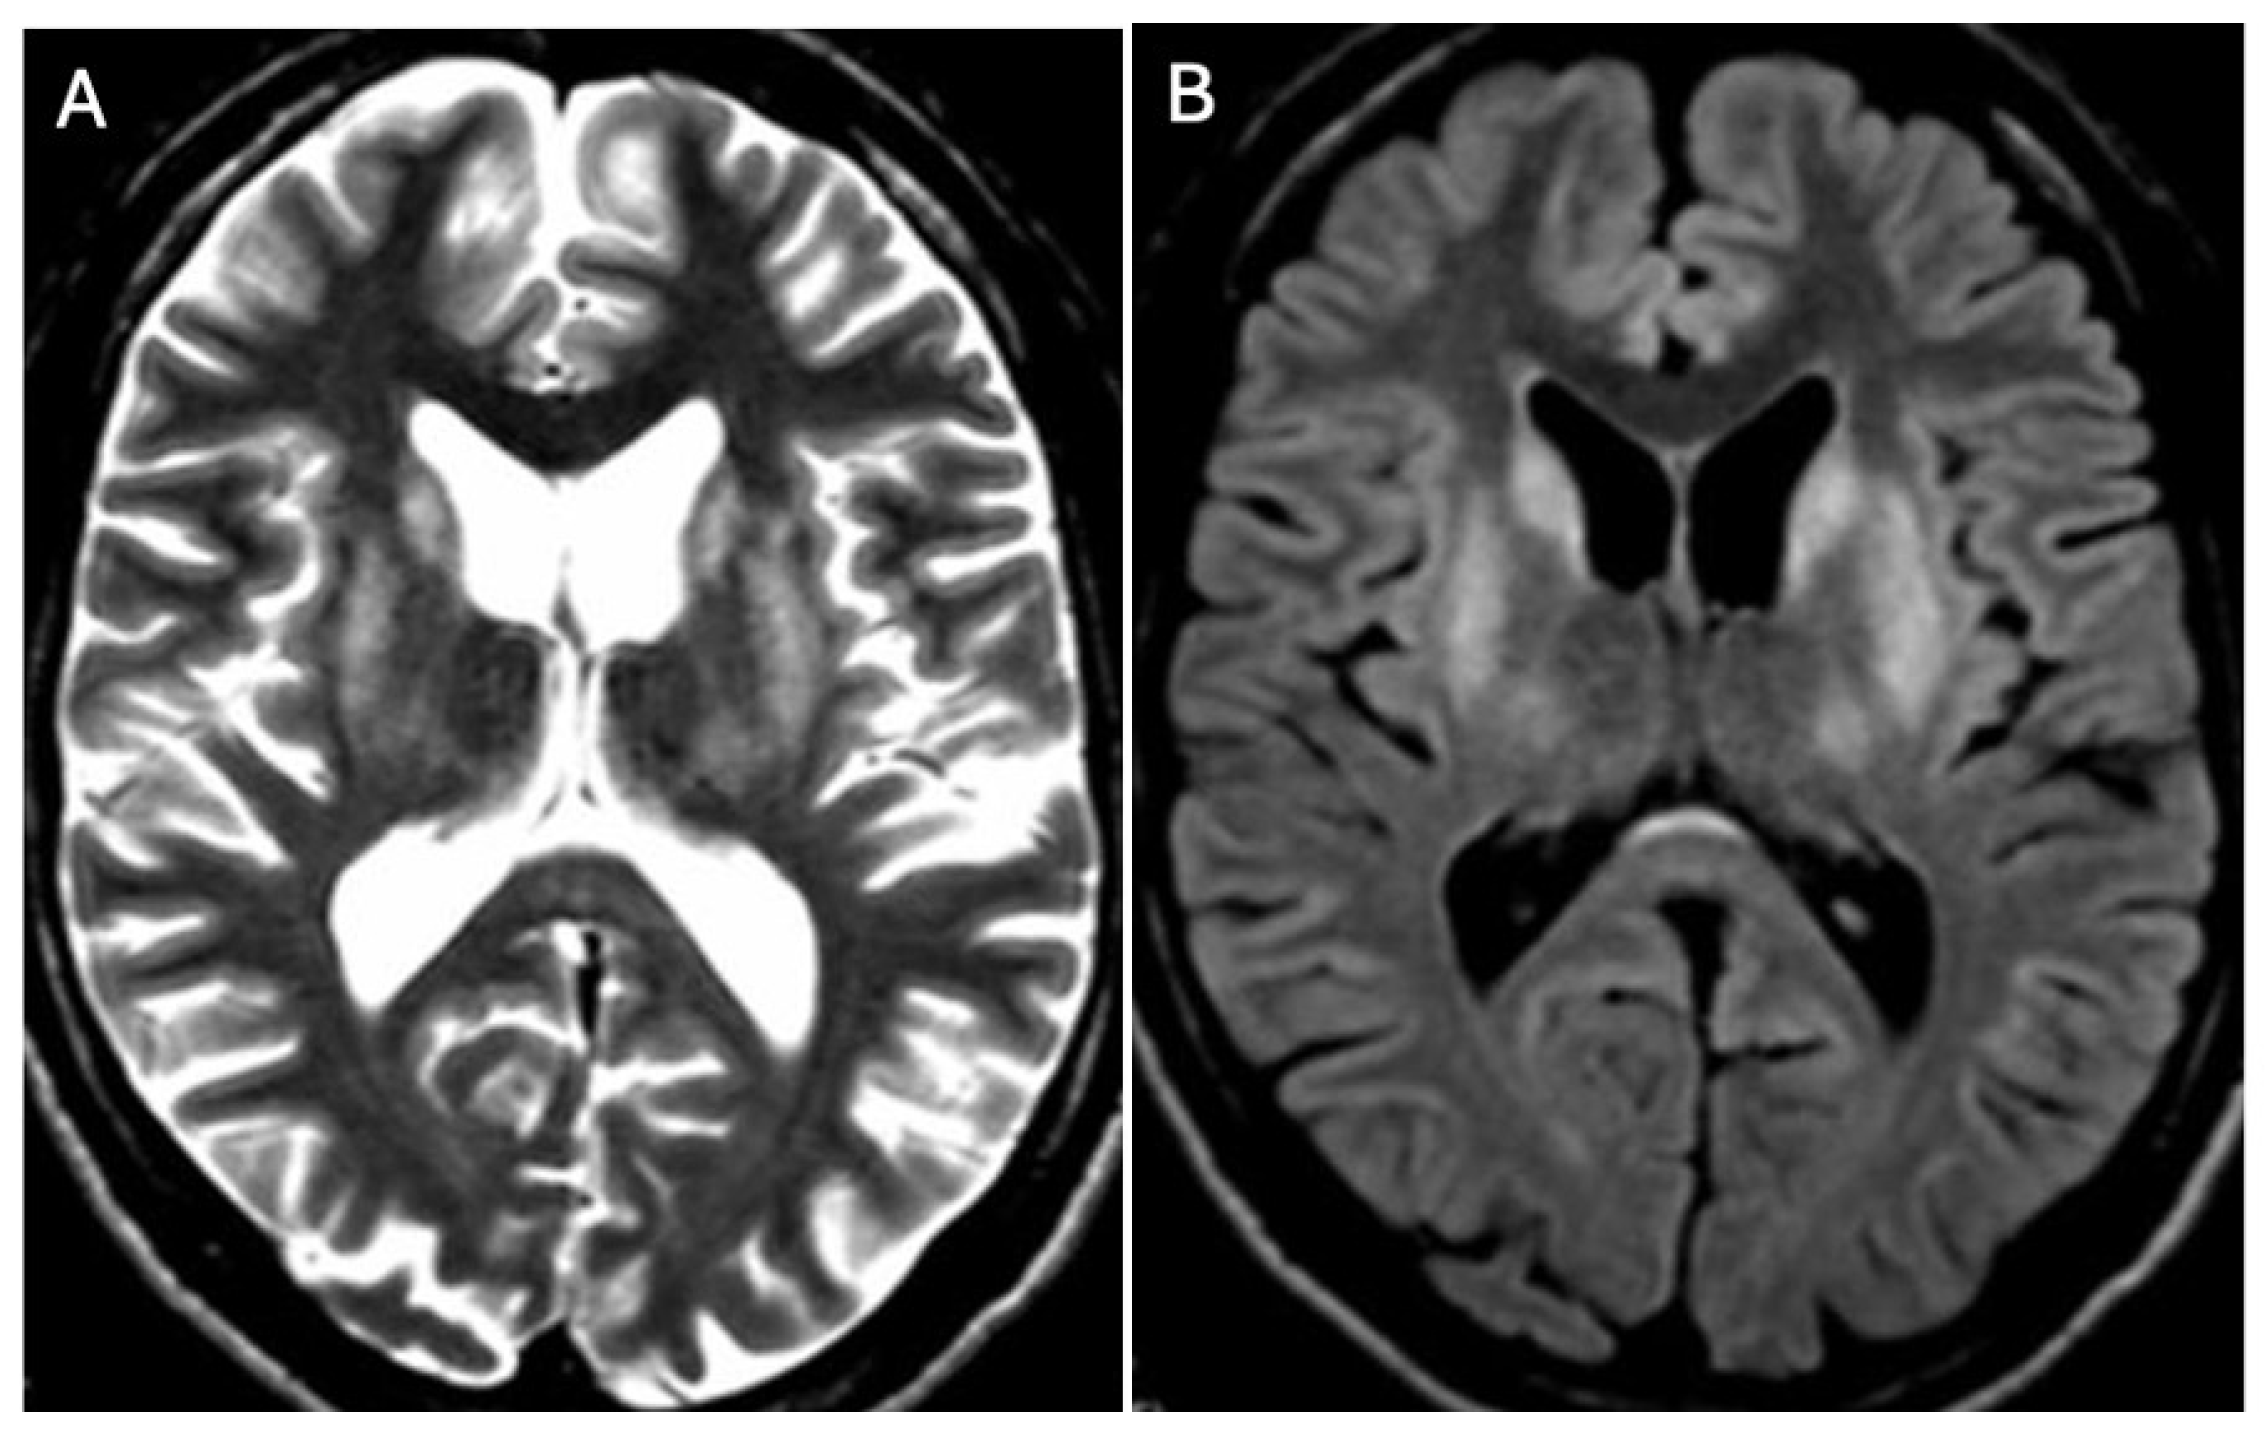

Brain MRI appears to be the most valuable neuroradiological examination for diagnosing WD, differentiating extrapyramidal symptoms, and monitoring anti-copper treatment. Classical brain MRI findings in WD typically include symmetric (rarely asymmetric) hyperintense or mixed-intensity changes in the basal ganglia (globus pallidus, caudate nucleus, thalamus, and/or pons) observed in fluid-attenuated inversion recovery (FLAIR) and T2-weighted sequences [9,12,13,14,15,16,17,18] (Figure 1A,B and Figure 2A,B).

Hyperintense changes localized in putamen, head of nucleus caudate, and thalamus in T2-weighted sequences (A) and FLAIR (B) (own materials of the neurology department).

Hyperintense changes localized in pons in T2-weighted images (A) and FLAIR (B) (own materials of the neurology department).